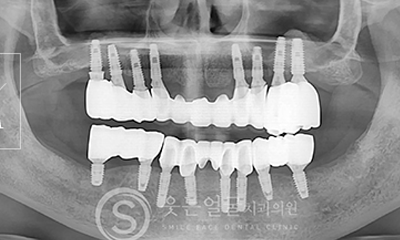

고난이도 임플란트

웃는얼굴치과는 풍부한 경험과 전문성을 바탕으로

일반적인 케이스는 물론,

고난이도의 임플란트 수술까지

안전하게 진행합니다.

뼈 이식이나 발치 즉시 식립 등 까다로운 조건에서도 정밀 진단과

체계적인 시술 시스템으로 환자 맞춤형 치료를 제공합니다.

• 고난도 임플란트 전문 진료

웃는얼굴치과는 난이도가 높은

임플란트 수술까지 정밀한 진단과 계획을

바탕으로 안전하게 치료합니다.